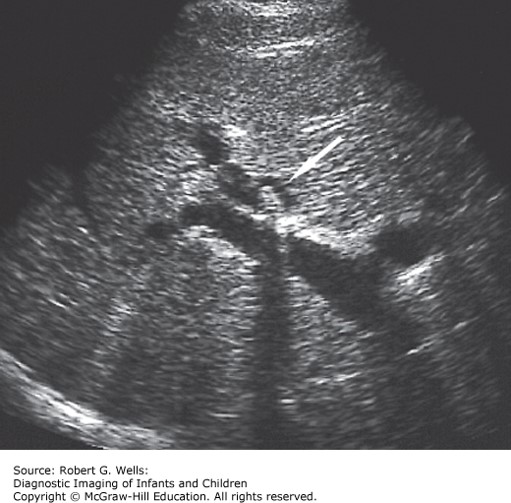

The correct answer is “B.” Choledocholithiasis refers to gallstones in the common bile duct. Pain, or “biliary colic,” arises when a stone temporarily obstructs the biliary tree. Children and adolescents present with right upper quadrant pain, vomiting, and sometimes jaundice. The stone should be removed surgically. Stone removal by endoscopic retrograde cholangiopancreatography (ERCP) is becoming more common.

Photo: Wells RG. Diagnostic Imaging of Infants and Children; 2015.